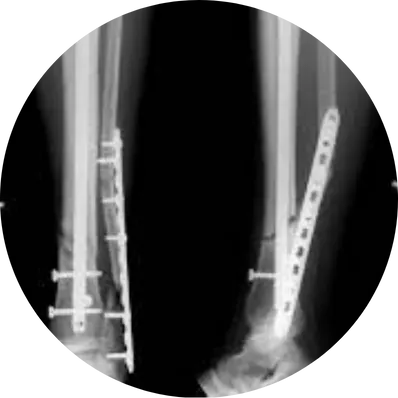

The surgeon makes a small incision over the fractured bone, gently exposes the fracture site, and realigns the bone fragments into their correct anatomical position. Stainless steel or titanium plates are then fixed using screws to stabilize the bone securely.

In cases of both-bone forearm fractures, each bone is individually plated using separateincisions. This ensures better stability, quicker healing, and prevents long-term deformity or arm weakness.

Real-time imaging is used during surgery to confirm perfect alignment of the bones andaccurate placement of plates and screws, ensuring optimal healing.

Under anesthesia, the fracture is realigned, and a metal plate is fixed to the bone with screws for stability. Healic uses compression or locking plates depending on fracture type for best healing.